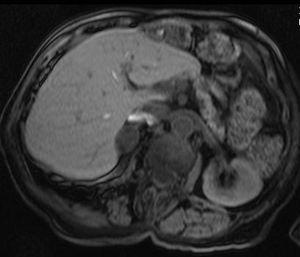

الكظرية

MRI scan T1 with fat saturation - adrenal adenoma

أورام الغدة الكظرية، وغالباً ما تنتشر في البطن، وفي العادة لا يتم التركيز على فحصها؛ وفي معظم الأحيان يتم اكتشافها بطريقة عرضية. واحدة من 10.000 منها خبيثة. وبالتالي، نادراً ما تستلزم أخذ عينة من الورم، خاصة لو كانت الآفة متجانسة وأصغر من 3 سنتيمتر. صور المتابعة لمدة تتراوح من ثلاثة إلى ستة أشهر يمكن أن تؤكد استقرار النمو.

بينما لا تفرز فيه أورام الغدد الكظرية أية هرمونات على الإطلاق، يفرز بعضها الكولسترول، مسبباً متلازمة كوشينگ، الألدوستيرون مسبباً متلازمة كون، أو الأندروجين مسبباً فرط الأندروجينية.